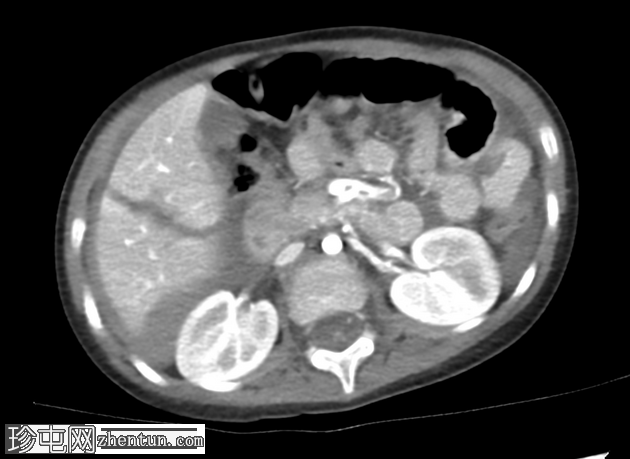

轴向C+门静脉期

AAST IV级肝撕裂伤,伴有大面积不规则肝损伤,累及V段(轴向、冠状、矢状)。

撕裂伤区域内未见活动性造影剂外渗。

可见中等量腹腔积血。

右髂前骨骨折。

无气腹。